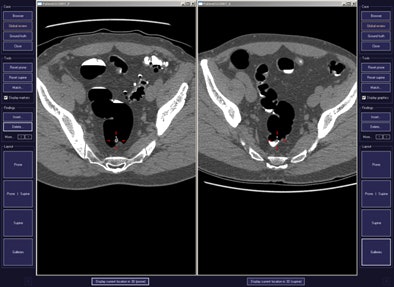

CAD first-reader gallery evaluation shown in a screening patient with a 10-mm tubular adenoma in the rectum. Above (left monitor), all 15 CAD markers in a volume are presented to the reader, line by line, as a collection of CT image galleries. They are sorted top to bottom by decreasing level of confidence, as computed by the CAD algorithm both for the prone (shown) or for the supine (not shown) position. CAD finding P:1 (first row of images) displays the polyp (crosshair) in all six gallery images. Note that the typical imaging characteristics of a polyp are already recognizable within the gallery images. The remaining CAD findings P:2-P:5 (image rows 2-5) display false-positive detections in the stomach (P:2), on the residual fluid layer (P:3), in the stomach (P:4), and in the terminal ileum. CAD findings P:6-P:15 are not shown. Below (right monitor), standard axial and optional coronal and sagittal 2D images (not shown). Optional 3D target views (not shown) of prone and supine datasets are used, first, to further evaluate potential polyp candidates or CAD findings on complex structures and, second, to perform a complete 2D review of the prone and the supine CTC datasets. The 2D axial prone and supine CT images show the polyp (crosshair) marked by CAD (marker 1) in both positions. All images courtesy of Dr. Thomas Mang.